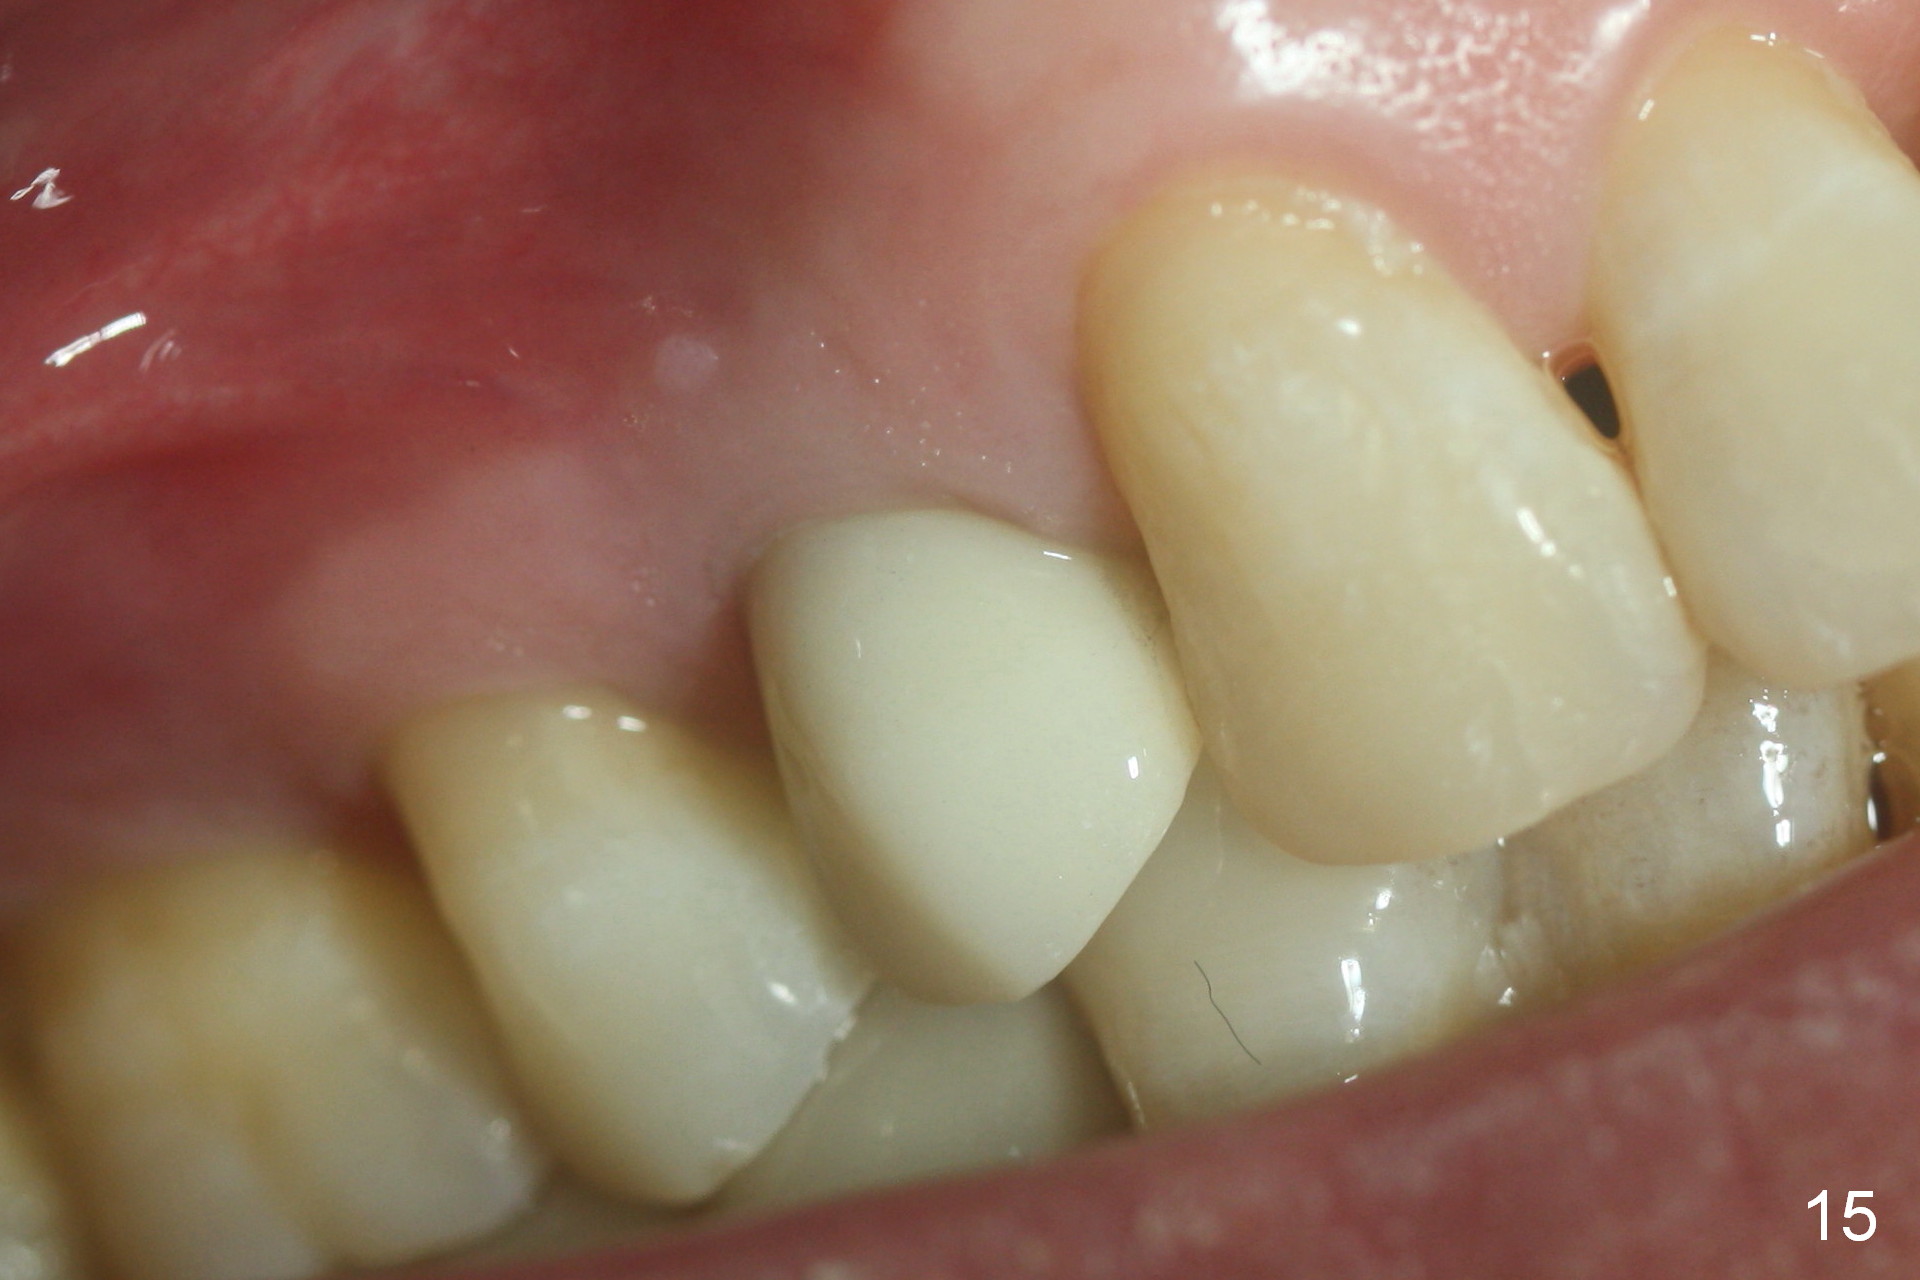

The patient returns 6 months postop for impression of a permanent restoration. The gingiva with knife-edged papillae adapts to the provisional (Fig.7). The gingiva looks healthy when the provisional is removed (Fig.8). The buccal bone resorption seems to be minimal, as compared to Fig.1,2. There is no bone loss between immediately postop (Fig.9 I; implant), 4.5 months postop (Fig.10 A: abutment), 4 and 7 months post cementation (Fig.11,12 C: crown). Soft and hard tissue morphology remains normal 7 months post cementation (Fig.13). No bone loss is observed 15 months post cementation (Fig.14). The papillae (Fig.15) and bone (Fig.16,17) remain stable 29 months post cementation.